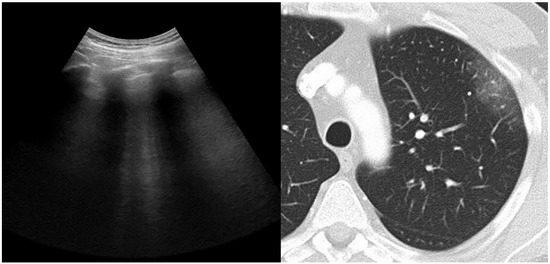

:1. Introduction

2.3. Chest Computed Tomography and Score Assessment

2.4. Lung Ultrasonography and Score Assessment